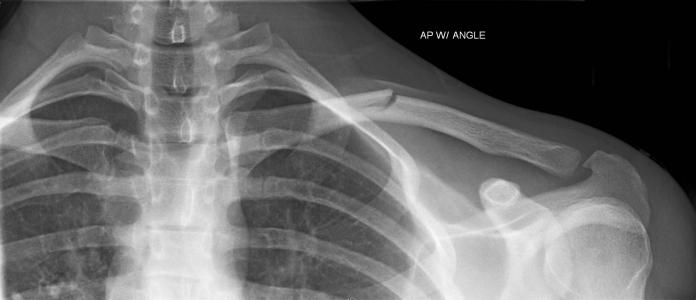

本病的辅助检查方法主要是影像学检查,锁骨骨折常发生在中段。多为横断或斜行骨折,内侧断端因受胸锁乳突肌的牵拉常向上后移位,外侧端受上肢的重力作用向内、下移位,形成凸面向上的成角、错位缩短畸形。

锁骨中段骨折

1.X线检查

疑有锁骨骨折时需摄X线像确定诊断。一般中1/3锁骨骨折拍摄前后位及向头倾斜45°斜位像。拍摄范围应包括锁骨全长,肱骨上1/3、肩胛带及上肺野,必要时需另拍摄胸片。前后位像可显示锁骨骨折的上下移位,45°斜位像可观察骨折的前后移位。

内侧断端因受胸锁乳突肌的牵拉常向上后移位,外侧端受上肢的重力作用向内、下移位,形成凸面向上的成角